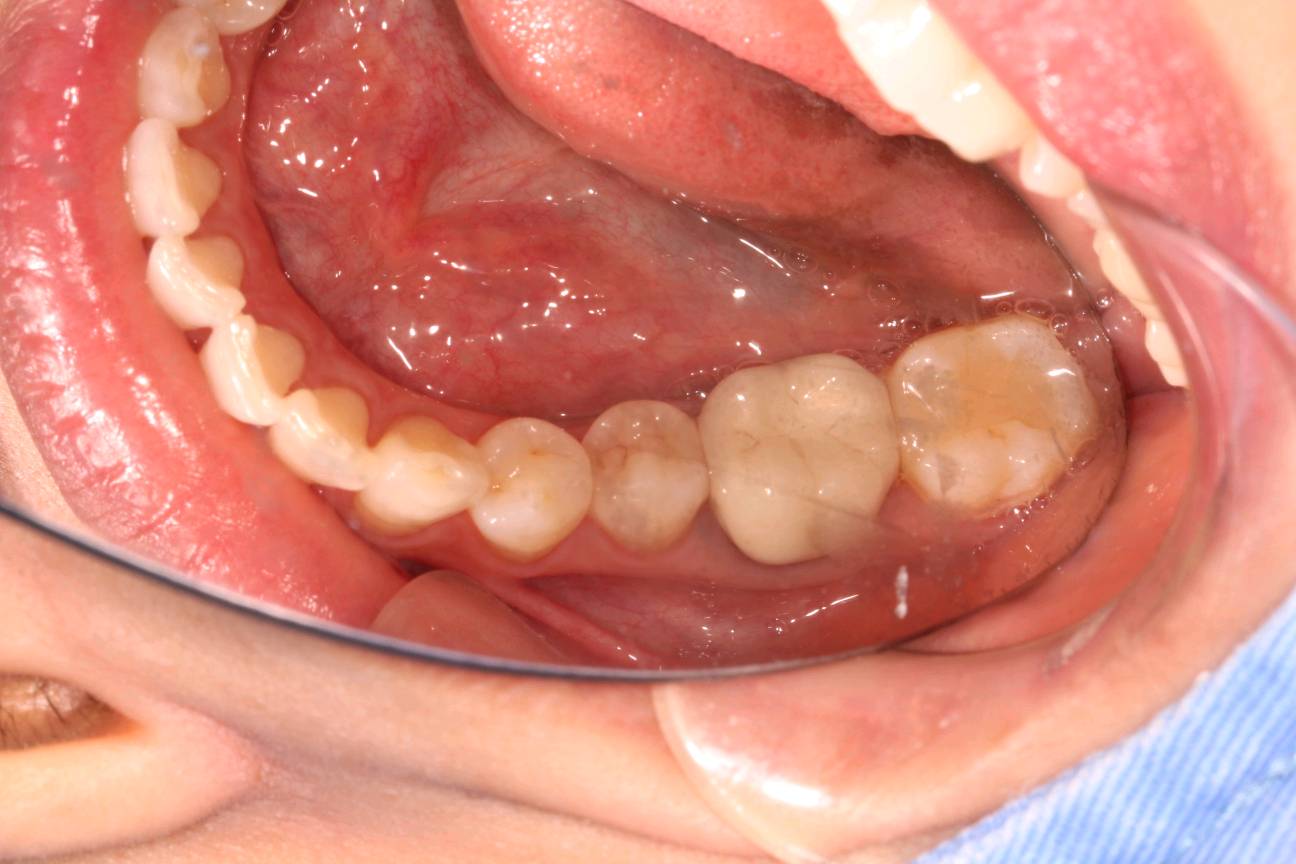

术前检查

图片发自160App